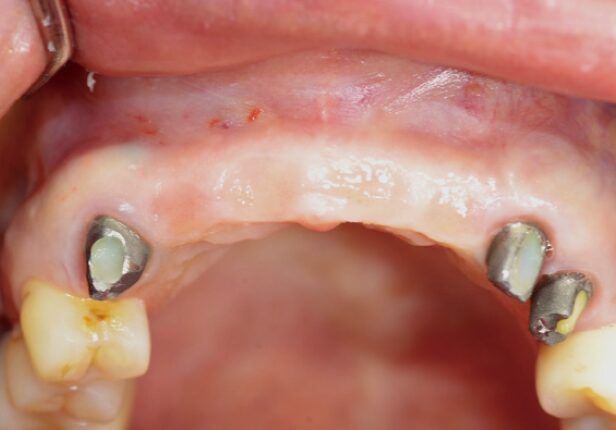

Antes da cirurgia

caso de estudo

Antes da colocação da coroa final